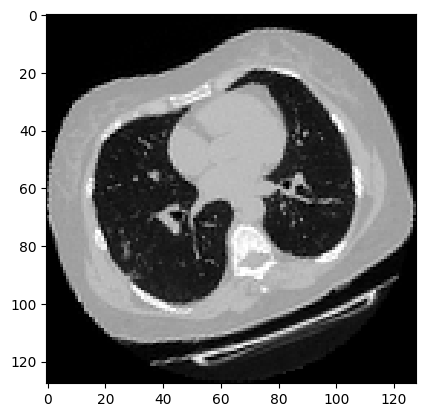

可视化增强型 CT 扫描。

images, labels = train_dataset.__getitem__(0)

print(images.shape)

image = np.squeeze(images, 3)

print("Dimension of the CT scan is:", image.shape)

plt.imshow(np.squeeze(image[:, :, 30]), cmap="gray")

plt.show()

(128, 128, 64, 1)

Dimension of the CT scan is: (128, 128, 64)

由于CT扫描有许多层切片,可视化多层切片。